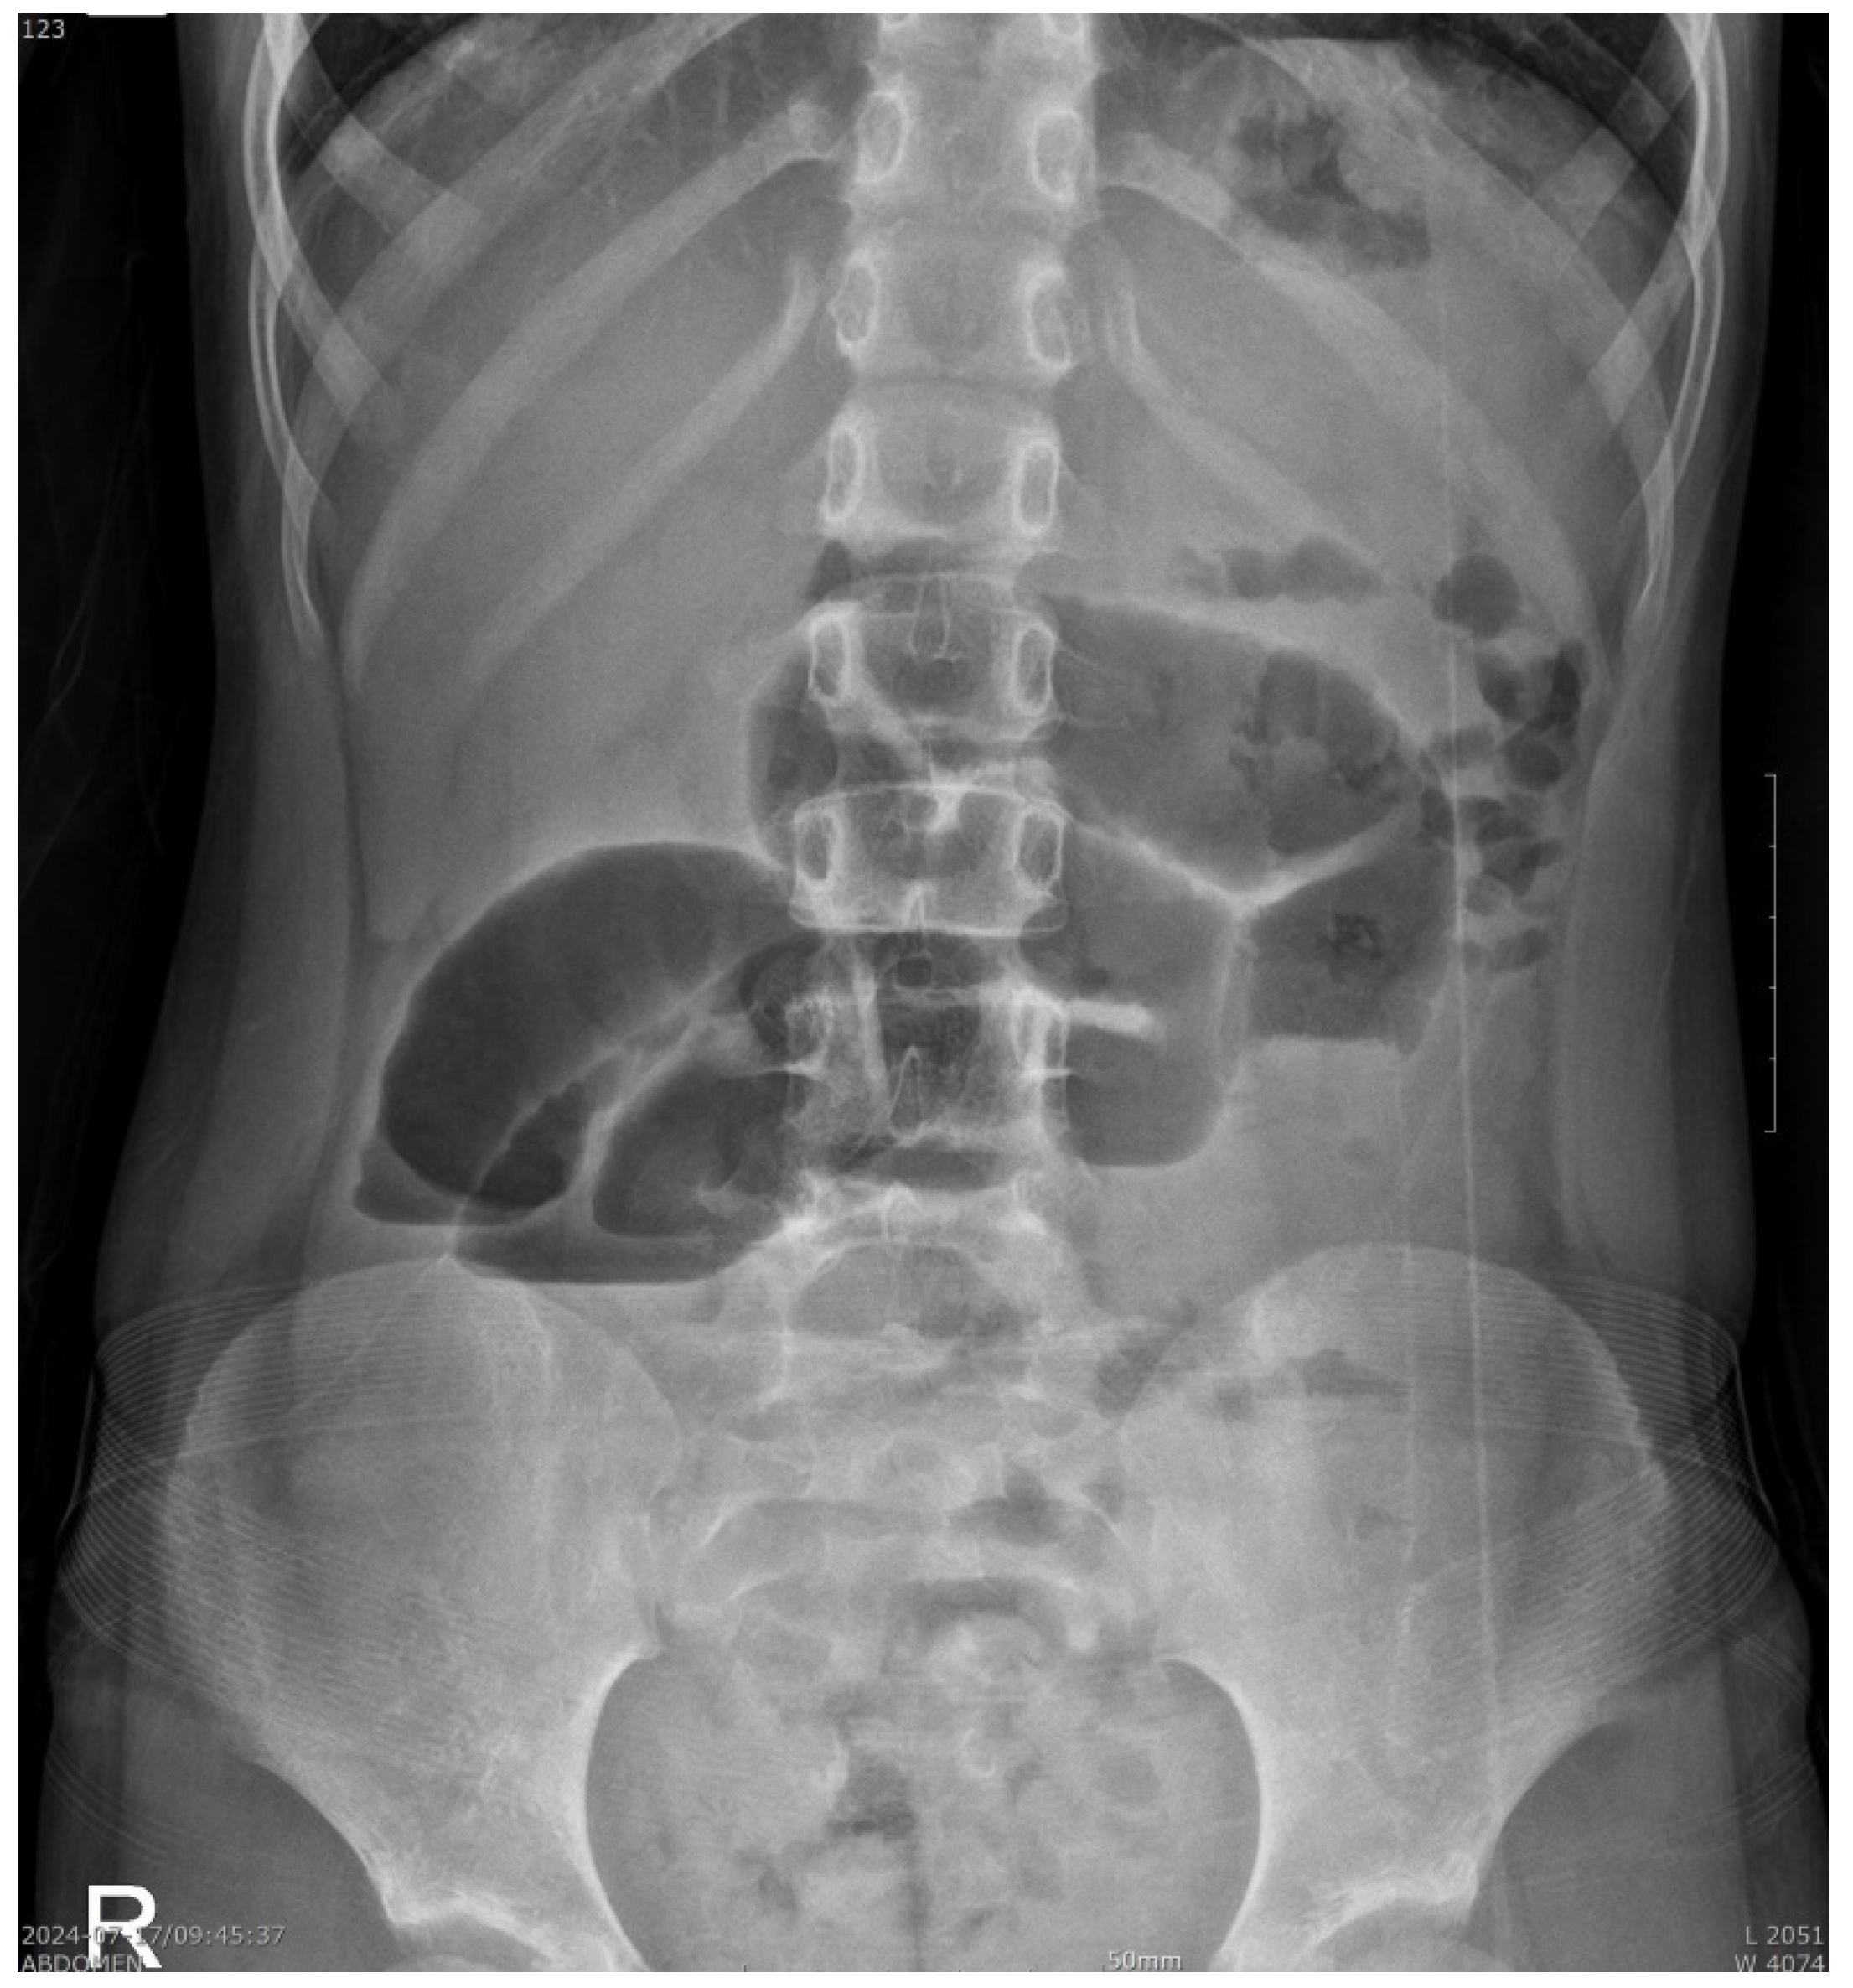

2. Case Presentation